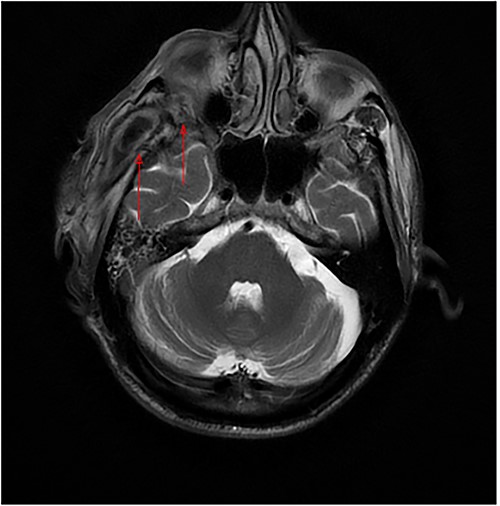

(a) Axial MRI of the head: a dumbbell-shaped lesion (red arrows) representing an infratemporal abscess invading the orbital cavity through the bony erosion of the lateral orbital wall. (b) Abscess localization in the deep temporal space (red arrows). (c, d) Coronal MRI of the head and neck shows an orbital abscess (red arrows) and endopthalmitis (red arrows).

Axial MRI of the head, a dumbbell-shaped lesion (red arrows) representing an infratemporal abscess invading the orbital cavity through the bony erosion of the lateral orbital wall.

Most cases of odontogenic orbital complications arise from upper jaw tooth infections [4]. What is unique about our case is the unusual route by which the infection spread into the orbit. In our case, the hypothesized path of spread started from the lower third molar infection to both the submasseteric and pterygomandibular spaces and then passed into the infratemporal fossa, where a focus of abscess was loculated, making its way into the orbit through a bony defect in the lateral orbital wall, forming an interesting dumbbell-shape appearance on MRI (Fig. 2a).